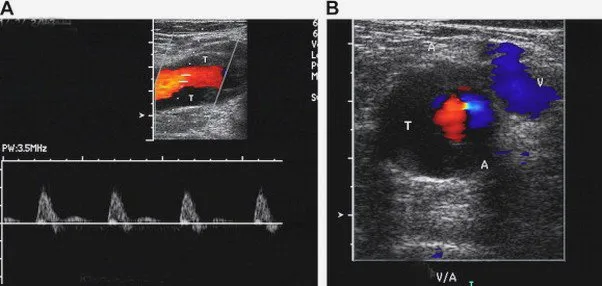

• Siêu âm Doppler: Sử dụng sóng âm để tạo ra hình ảnh về các mạch máu và dòng chảy của máu.